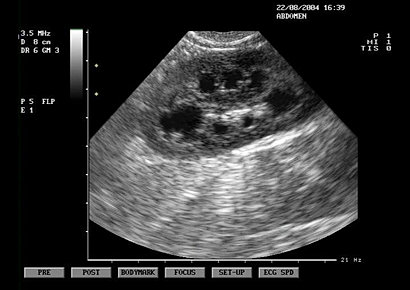

Abdominal Ultrasound . Frequently Asked Questions. Question: What is an ultrasound? Answer: An ultrasound is an examination that uses high-frequency ... Fetch Document

Abdominal Complete Ultrasound What is an Abdominal Complete Ultrasound? 76705 abdominal limited (one organ or quadrant is scanned) Indications nausea, vomiting, abdominal pain, abnormal blood work, history of cancer, follow-up on abnormal x-ray, MRI or CT scan ... Access Full Source

This means that while per-forming serial scans, you will view many sections of the liver more than once but are apt to miss blind spots if you are not fully familiar with the Abdominal Ultrasound: Step by Step (ISBN 9783131383624), © 2012 Georg Thieme Verlag KG Fig.4.1 Approaches for scanning ... Doc Viewer

Abdominal Ultrasound How, Why and When SECOND EDITION It is fair to say that the safety of ultrasound is less of an issue in abdominal scanning than in obstetric or reproductive organ scanning. means that there is continuous forward flow ... Document Viewer

Abdominal ultrasound means applying an extraordinary advance in the diagnosis and evaluation of emergency physicians, being transcendental training of this techni- young women. Advantages of abdominal ultrasound in the EF. Critical ... Fetch Content